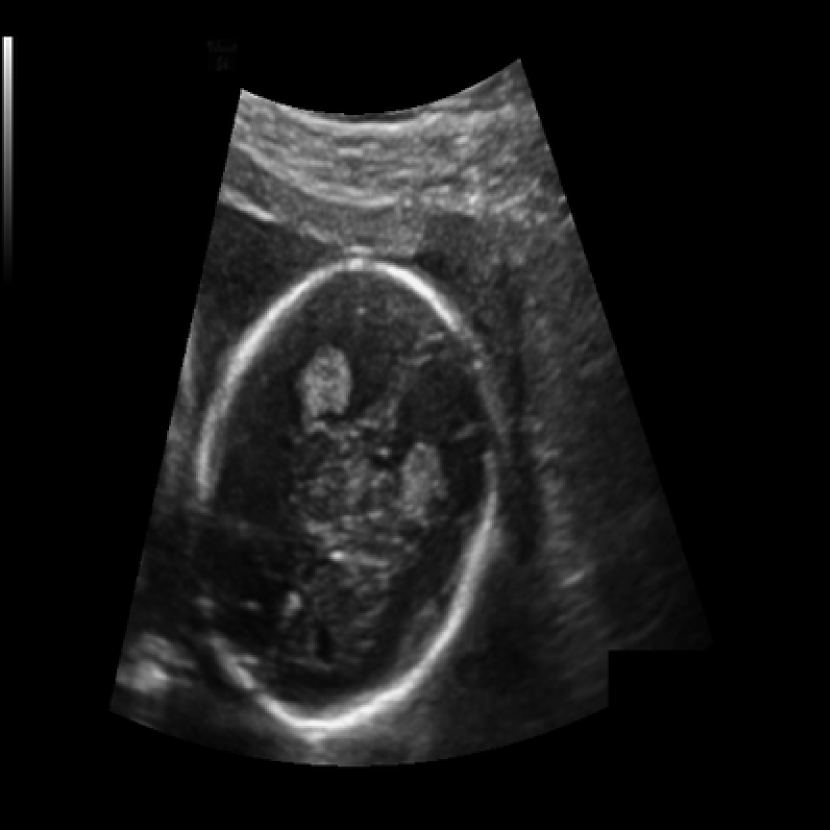

The 2D - USG dataset is used as the main training dataset for U-WNO. The image dataset comprises ultrasound images sourced from HC18 challenge111https://hc18.grand-challenge.org/. Each image has been resized to the shape of 128*128 pixels and is stored in PNG format. The dataset includes two-dimensional ultrasound scans from various stages of pregnancy across different trimesters. It consists of approximately 976 images and their corresponding masks, which were converted into filled masks, with the fetal head designated as the target label, as shown in Figure 1. The model was inferenced over the test set containing around 325 images in the same format. This facilitates model training, hyper-parameter tuning, and unbiased evaluation. Each subset maintains a balanced representation to prevent any bias in the learning process and to ensure it’s generalization across different scenarios.

Figure 3 shows representative samples of the output generated by applying U-WNO on the test set. These visualizations underscore the model’s capability to discern intricate patterns despite the noisy background and reduced image size.